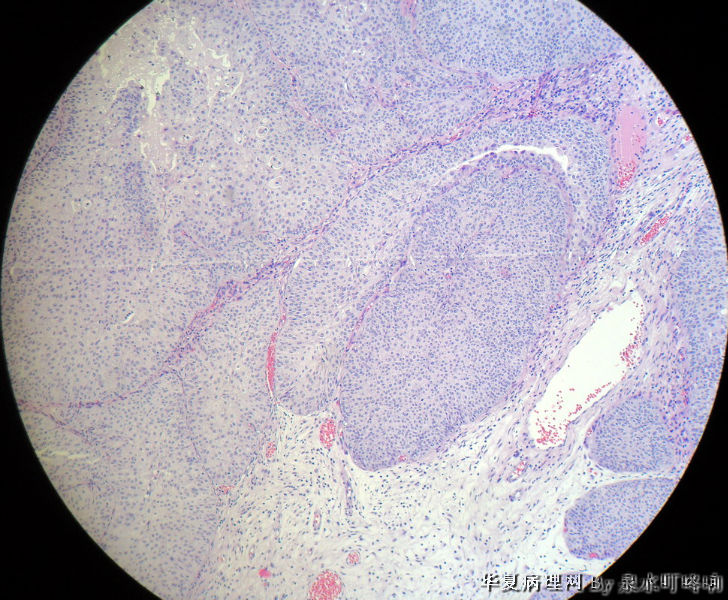

膀胱肿物

膀胱肿物图2

名称:图2

描述:2

男,76岁,血尿一个月,发现膀胱肿物,行切除术,肿物位于右侧膀胱后外侧壁,约1.5×1.5×1.5厘米。

大体:灰白肿物一个,大小约2×1.1×0.9厘米,切面灰白,质中。

尿路上皮癌,低级别。

低级别非浸润性乳头状尿路上皮癌

(膀胱)非浸润性乳头状尿路上皮癌,低级别

低级别尿路上皮癌。至于浸润的问题还请楼主仔细观察切片,总感觉那种推进式的生长模式有浸润的嫌疑,临床上浸润与否治疗方式是不一样的。

Dx: High grade papillary urothelial carcinoma because: 1. nuclear chromasia (fig 13) and coarse chromatin. 2, almost all nuclei have prominent  nucleoli. 3, Nuclear pleomorphism (some nuclei are three times larger than smaller ones). 4. Nuclear membrane irregularity. 5. mitosis can be seen far away from the basement membrane. 6. a good portion of the neoplastic cells loss orientation that should be perpendicular to the basement membrane. 7. Low power view shows papillary branching and fusion. 8. patient's age

However, this should be the low end of the spectrum of high grade urothelial carcinoma. Careful search might reveal some focal microinvasion.or urothelial carcinoma in situ.